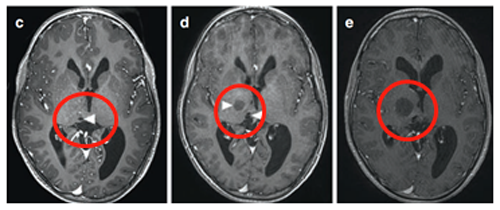

9岁男童出现左面部、上肢和下肢急性症状3周,持续轻微口齿不清超过三个月。体查发现多处咖啡色斑点和腋窝雀斑,曾诊断为注意缺陷多动障碍。

轴位MRI造影剂及冠状面T2-WI显示右侧丘脑结节状肿瘤呈环形增强。肿瘤累及内侧颞叶结构,Rutka教授制定综合治疗方案:先行经颞中回经脑室入路次全切除肿瘤,病理确诊为WHO I级毛细胞星形细胞瘤,BRAF重复融合状态阴性。免疫组化检测BRAF V600E、H3K27M均为阴性。基因检测证实NF1基因变异。

术后六个月影像显示丘脑部分切除和中脑肿瘤残留,据此制定个性化辅助治疗计划,患儿对放疗反应良好。